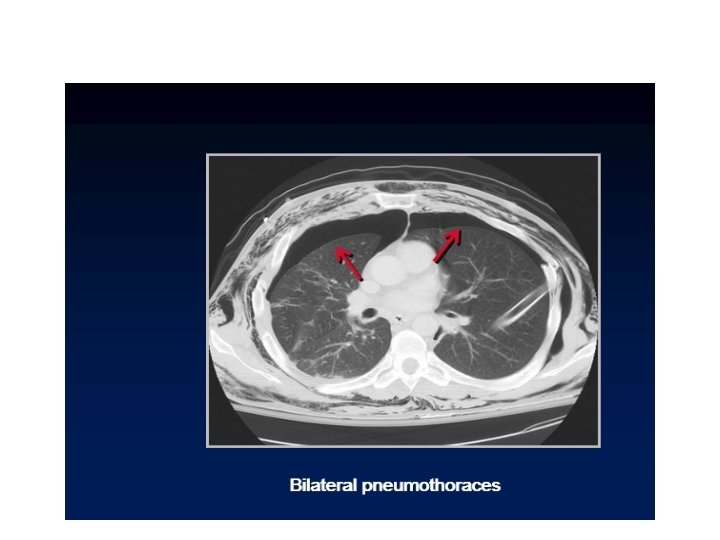

Pneumo thorax due to pulmonary laceration